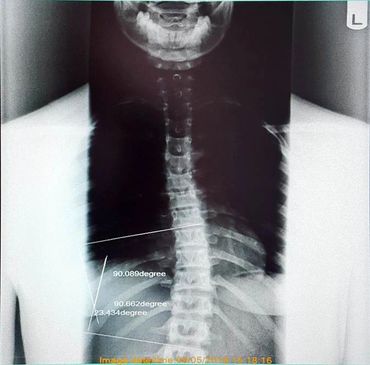

A 15 year old, competitive, cheerleader came in to the clinic with upper and lower back pain after having someone fall on them from a height during a practice. Upon examination and an x-ray of their thoracic spine (mid back) we measured a curve of 24 degrees. After 6 short months of chiropractic treatment and Myopulse, and a re-examination and x-ray the curve reduced to 4 degrees and is no longer classified as scoliosis! Both the patient and their family are happy with the decrease in tightness and pain and the patient's improved performance on their cheer squad!